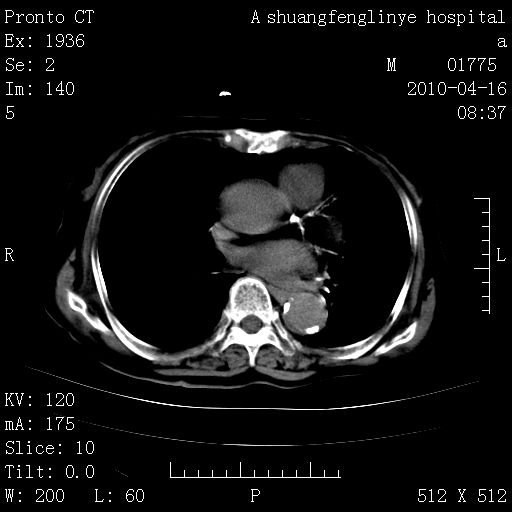

陈旧性结核,胃腔扩大,脾脏受压后移

老年肺间质纤维化,肺动脉高压-----肺心病。

典型 夹层动脉瘤。 内膜瓣钙化移位

1)左肺上叶结核(纤维、增殖病灶)。2)冠状动脉及主动脉钙化。肺动脉高压